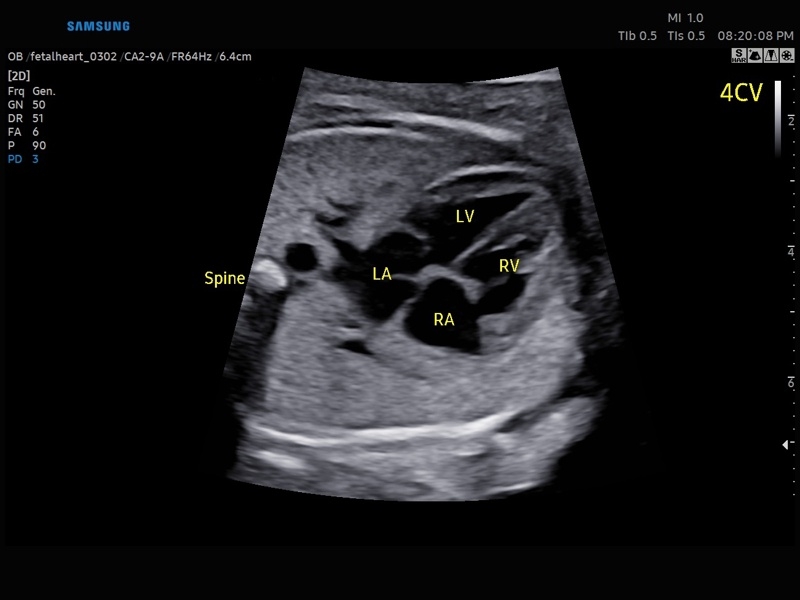

• МодульSTIC- объемная динамическая визуализация сердца плода.

• Сердце плода:измерения в В-режиме (отношение площади сердца и грудной клетки), измерения в М-режиме (толщина межжелудочковой перегородки в диастолу, конечнодиастолический размер левого желудочка, толщина задней стенки левого желудочка в диастолу, толщина межжелудочковой перегородки в систолу, размер левого желудочка в систолу, толщина задней стенки левого желудочка в систолу, внутренний размер правого желудочка в диастолу), измерения в режиме спектрального допплера (легочный ствол, артериальный проток, нижняя полая вена, венозный проток, восходящая аорта, нисходящая аорта, трансмитральный кровоток, митральная регургитация, трикуспидальный кровоток, трикуспидальная регургитация, индекс преднагрузки, ЧСС).